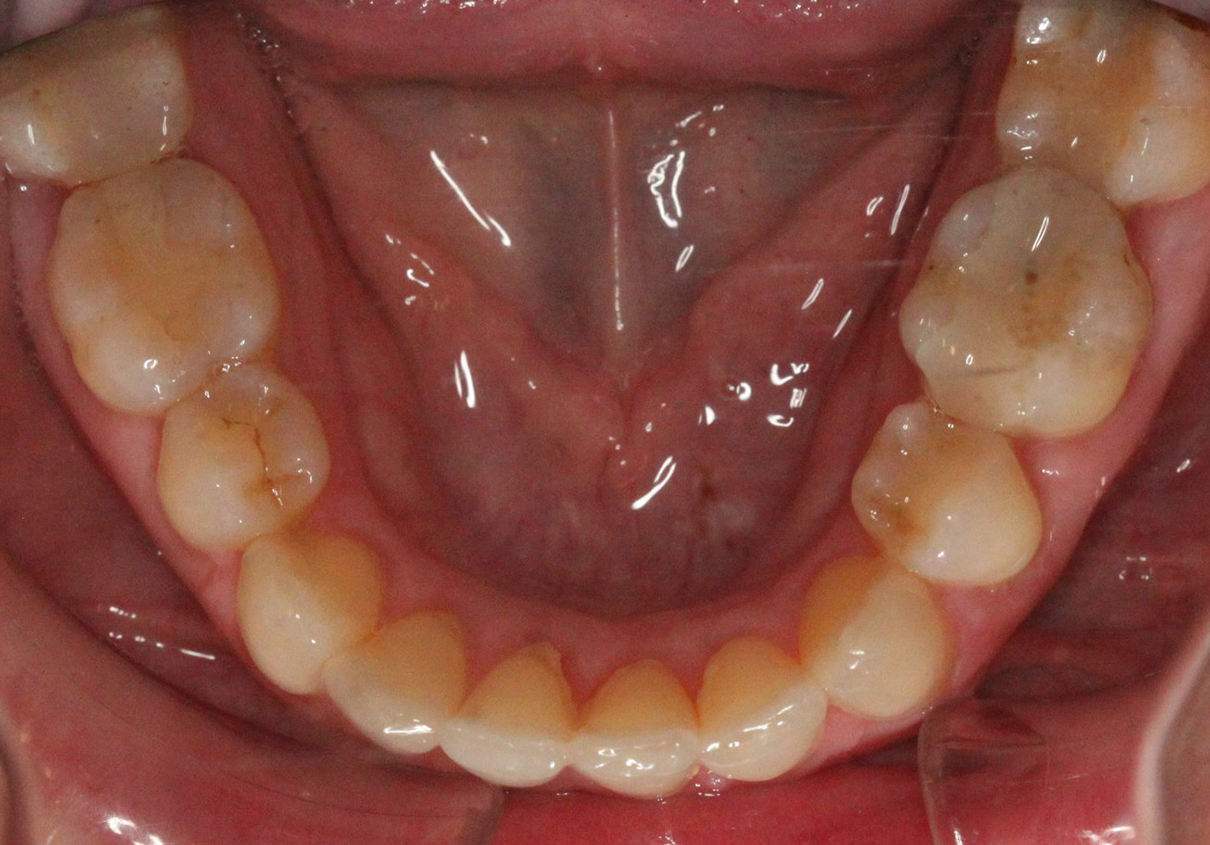

Implant restoration in the esthetic zone often requires well-coordinated interdisciplinary care in order to achieve ideal treatment results. This is especially the case when implants are planned to replace periodontally hopeless teeth. When teeth are extracted, we can typically anticipate 2mm of facial recession. If implants are to be placed following the extraction of hopeless teeth with an already existing gingival height discrepancy, the discrepancy will likely be exacerbated.

Extraction after forced eruption can allow for a much more favorable implant site compared with extraction alone. This is possible because the tension applied to the periodontal ligament during orthodontic tooth movement stimulates osteoblastic activity to induce new bone formation. As the tooth moves coronally during extrusion, soft tissue and bone attached to the periodontal fibers migrate in the same direction. As a result, forced eruption can be used to enhance the quality and quantity of both hard and soft tissue of future implant sites.

The special report presented below illustrates how orthodontic extrusion was successfully used to improve the periodontal architecture prior to the placement of two adjacent implants in the esthetic zone and thus allowed for a more ideal restorative result.